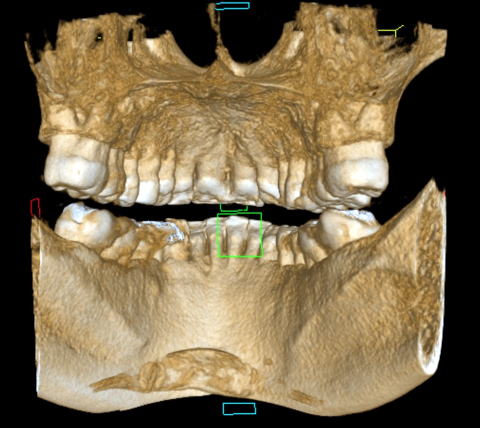

である。開業当初から当診療システムで38年間口腔管理をしている。Panorama、CTなどレントゲンを介しての顎骨・歯槽骨の形態・骨

量などを観察したもので、歯槽骨の吸収状態から診ても、ほぼ二十歳代に相当するように思われる。過去の論文を見ても、口腔内写真

■Volume Rendering(CT)

(図15)2015年7月27日、83歳。高年齢と残存歯数ばかりが問題視されているが、歯槽骨の状態、歯肉、Pocketの状態を含めた歯周病を評価すべきである

歯周病治療38年経過:83歳(女性)残存歯数28本